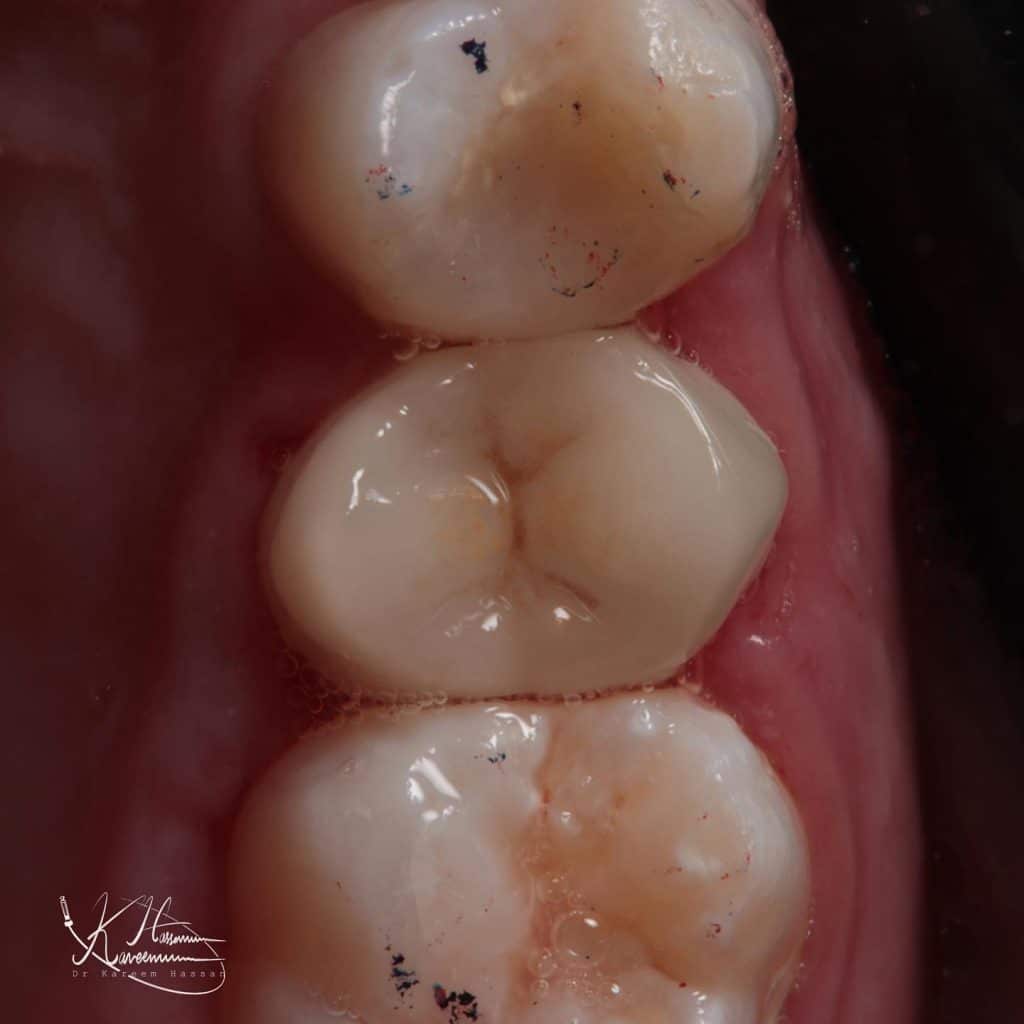

Initial situation

Check occlusion